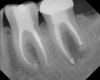

Figure 7  Clinical case of internal root resorption that was treated by orthograde root canal therapy.

Figure 7